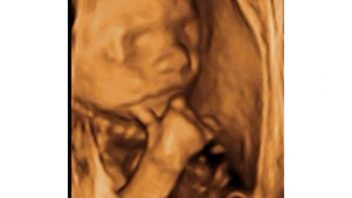

6.10.2010 4D ultrazvuk